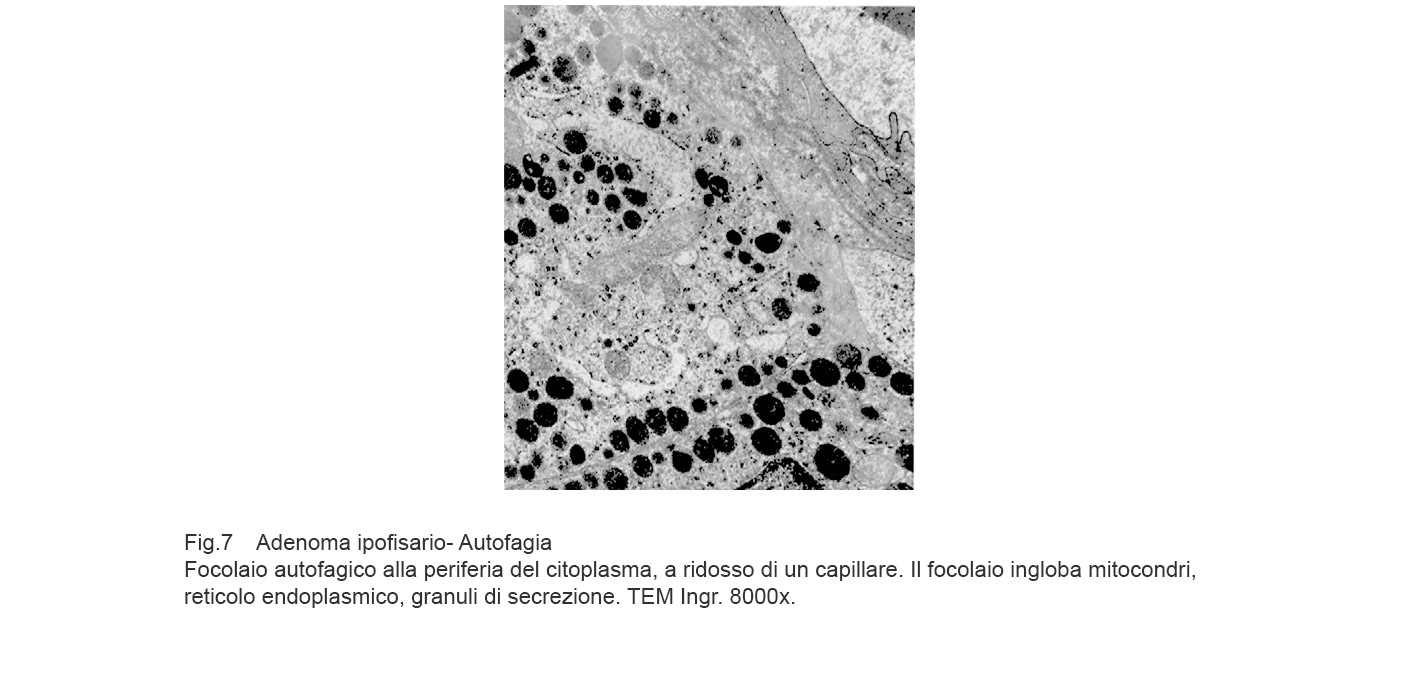

I focolai di autofagia sono di grandezza diversa e sono caratterizzati da una membrana a doppio strato e da contenuti rappresentati da frammenti di reticolo endoplasmico, da mitocondri in varie fasi di degradazione, da gocce lipidiche, da granuli di secrezione, da ribosomi, da microtubuli e da materiale amorfo.

Gli aspetti ultrastrutturali qui riscontrati sono conseguenti non solo alla tipologia delle substrutture inglobate ma anche alla fase di degradazione nella quale cade l’osservazione microscopica. E’ possibile documentare la esistenza di un focolaio di autofagia inglobante mitocondri, reticolo endoplasmico, microtubuli e citosol ancora in discreto stato di conservazione.

Se il focolaio autofagico si forma lungo la fascia periferica del citoplasma, a ridosso della membrana plasmatica e spesso a ridosso della parete di un capillare, si concretizza il rischio di una rottura del focolaio e svuotamento del contenuto negli spazi intercellulari o in modo mediato nel lume del vaso.

Fig.7